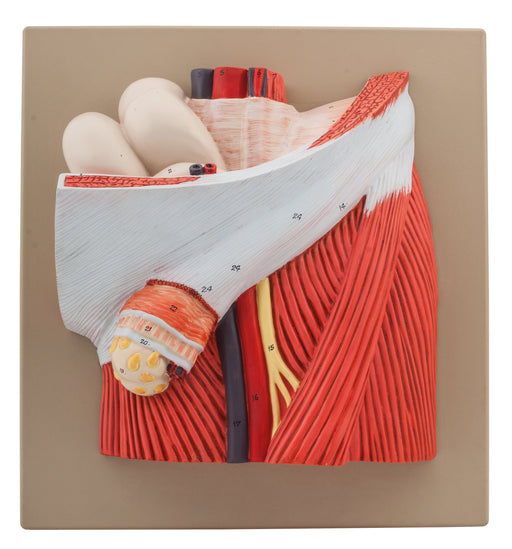

Hernia

This 2 times enlarged model of inguinal hernia shows the anatomical structures of a male groin with an indirect inguinal hernia, opened in layers. ...

View full detailsAM16047 -